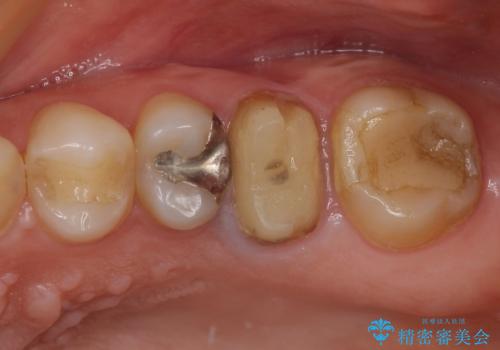

開咬により奥歯のみが接触している状態で、前歯部にほとんど接触のない状態で、奥歯に非常に負担のかかる咬み合わせでした。

また、欠損や根管治療の必要な歯など、むし歯による問題も多く散見されました。

まずはむし歯の治療を行い、その後ワイヤー矯正にて咬み合わせを改善し、途中インプラント埋入を行い、矯正治療後に補綴治療を行うこととしました。